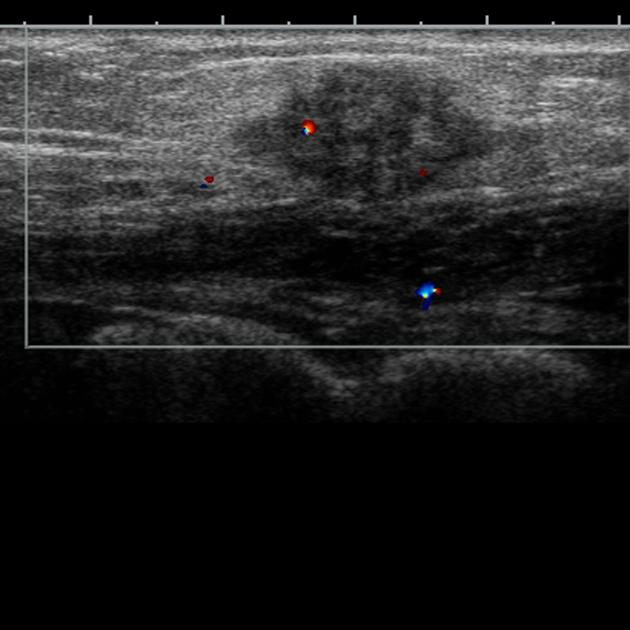

O diagnóstico, como mencionado anteriormente, é clínico. Entretanto, o exame de imagem é fundamental para confirmá-lo, bem como para determinar a extensão da doença.

Assim, os melhores exames para avaliar a endometriose são a ultrassonografia (USG) transabdominal ou transvaginal e a ressonância magnética (RM).